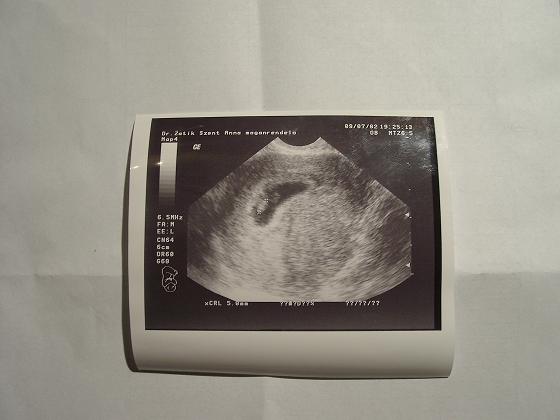

Sziasztok!!! Megjöttem a doki bácsitól, van szép kis szívverésünk, meg szép nagyok vagyunk: 5mm./CRL/ Nekem nem csinált semmi mást csak 1 hüvelyi ultrahangot, mondta, hogy Ő ezt nem zaklatja jobban, minden rendben van. Elmondtam mit szedek, azt mondta, hogy tökéletes, kérdezte van-e kérdésem, mondtam, hogy nincs, ha baj van jövök, egyébként meg a 12.héten jövök megint.. Ő csinálja a nyakiredő mérést, UH-ból van PhD-je.

Hát ennyi, mindjárt rakok fel egy képet is róla! /csak szokás szerint tölteni kell az aksikat.

Hát íme a topikunk februári babája: /nem túl jó a minőség, de most csak ilenre futotta/ :lol: